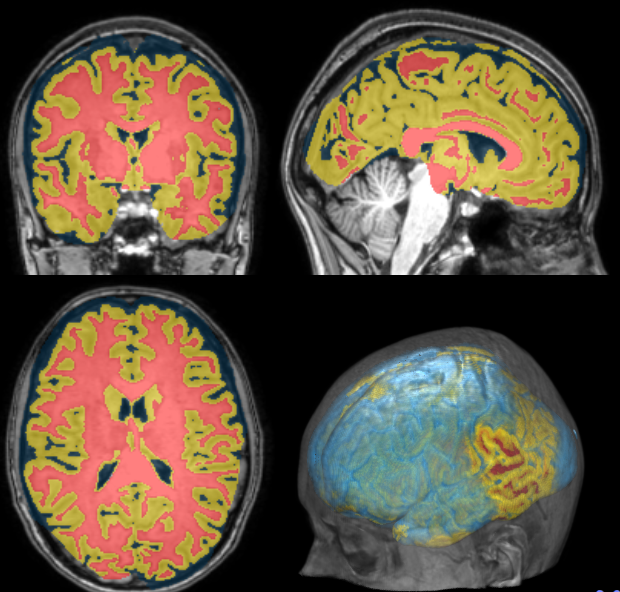

Segmentation

Cortical Thickness Estimation